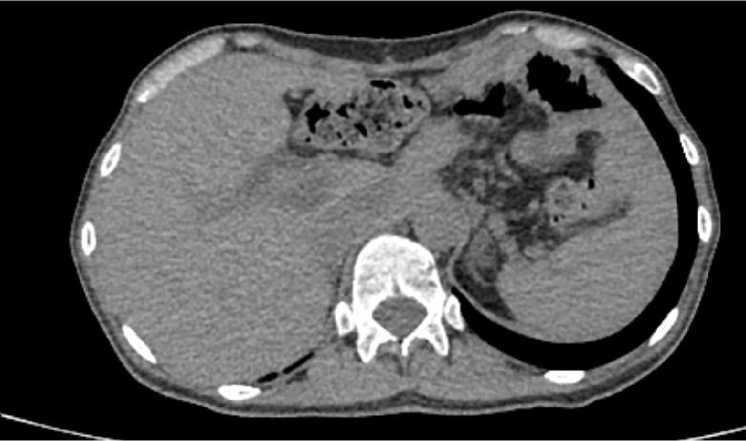

В раннем реабилитационном периоде (на амбулаторном этапе) выполнялись исследование электролитов (калий, натрий, хлор), общий (гемоглобин, эритроциты, нейтрофилы, ретикулоциты, тромбоциты) и биохимический (альбумин, мочевина, креатинин, глюкоза, АСТ, АЛТ, СРБ, общий билирубин, амилаза) анализы периферической крови (на 10-е, 20-е, 30-е сут). Значимых отклонений не определено. По данным контрольных исследований, включавших в себя КТ (рис. 9), ЭФГДС (рис. 10), УЗИ периферических лимфатических узлов, через 10, 20 и 40 нед. после хирургического лечения прогрессирования опухолевой патологии не отмечено.

Рис. 9. Компьютерная томография после 6 курсов лечения и выполненной гастрэктомии: 40 недель динамического наблюдения

Fig. 9. Computed tomography scan after 6 treatment cycles and gastrectomy. 40 weeks of follow-up